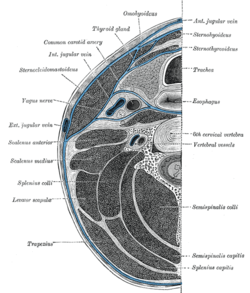

Section of the neck at about the level of the sixth cervical vertebra. Showing the arrangement of the fascia coli. | |

The scalene muscles have an important relationship to other structures in the neck. The brachial plexus and subclavian artery pass between the anterior and middle scalenes.[5] The subclavian vein and phrenic nerve pass anteriorly to the anterior scalene as the muscle crosses over the first rib. The phrenic nerve is oriented vertically as it passes in front of the anterior scalene, while the subclavian vein is oriented horizontally as it passes in front of the anterior scalene muscle.[5]

The passing of the brachial plexus and the subclavian artery through the space of the anterior and middle scalene muscles constitute the scalene hiatus (the term "scalene fissure" is also used). The region in which this lies is referred to as the scaleotracheal fossa. It is bound by the clavicle inferior anteriorly, the trachea medially, posteriorly by the trapezius, and anteriorly by the platysma muscle.